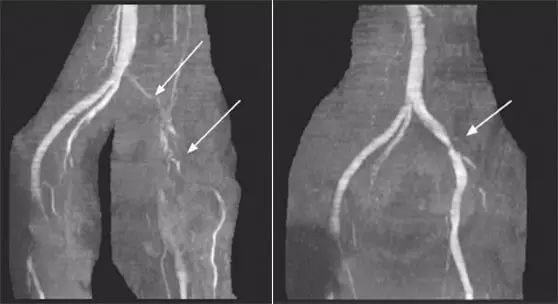

83 岁老年女性,因腰椎滑脱伴椎管狭窄引起难治性坐骨神经痛,行 L5/S1 后外侧脊柱融合术。术后第 2 天突然出现左下肢肿胀,MRI 检查提示一小骨块前移压迫左髂总静脉并伴 DVT;二次手术取除该小骨块后,左下肿胀很快消失。术后应用肝素和华法林预防深静脉血栓形成,6 月后复查原先 DVT 消失且无新的 DVT 发生 。

图 2 第二次手术术前(左)及术后(右)磁共振静脉图像。左图箭头所指为髂总静脉阻塞后的充盈缺损区,右图箭头所指为原阻塞解除后髂总静脉血流恢复通畅。